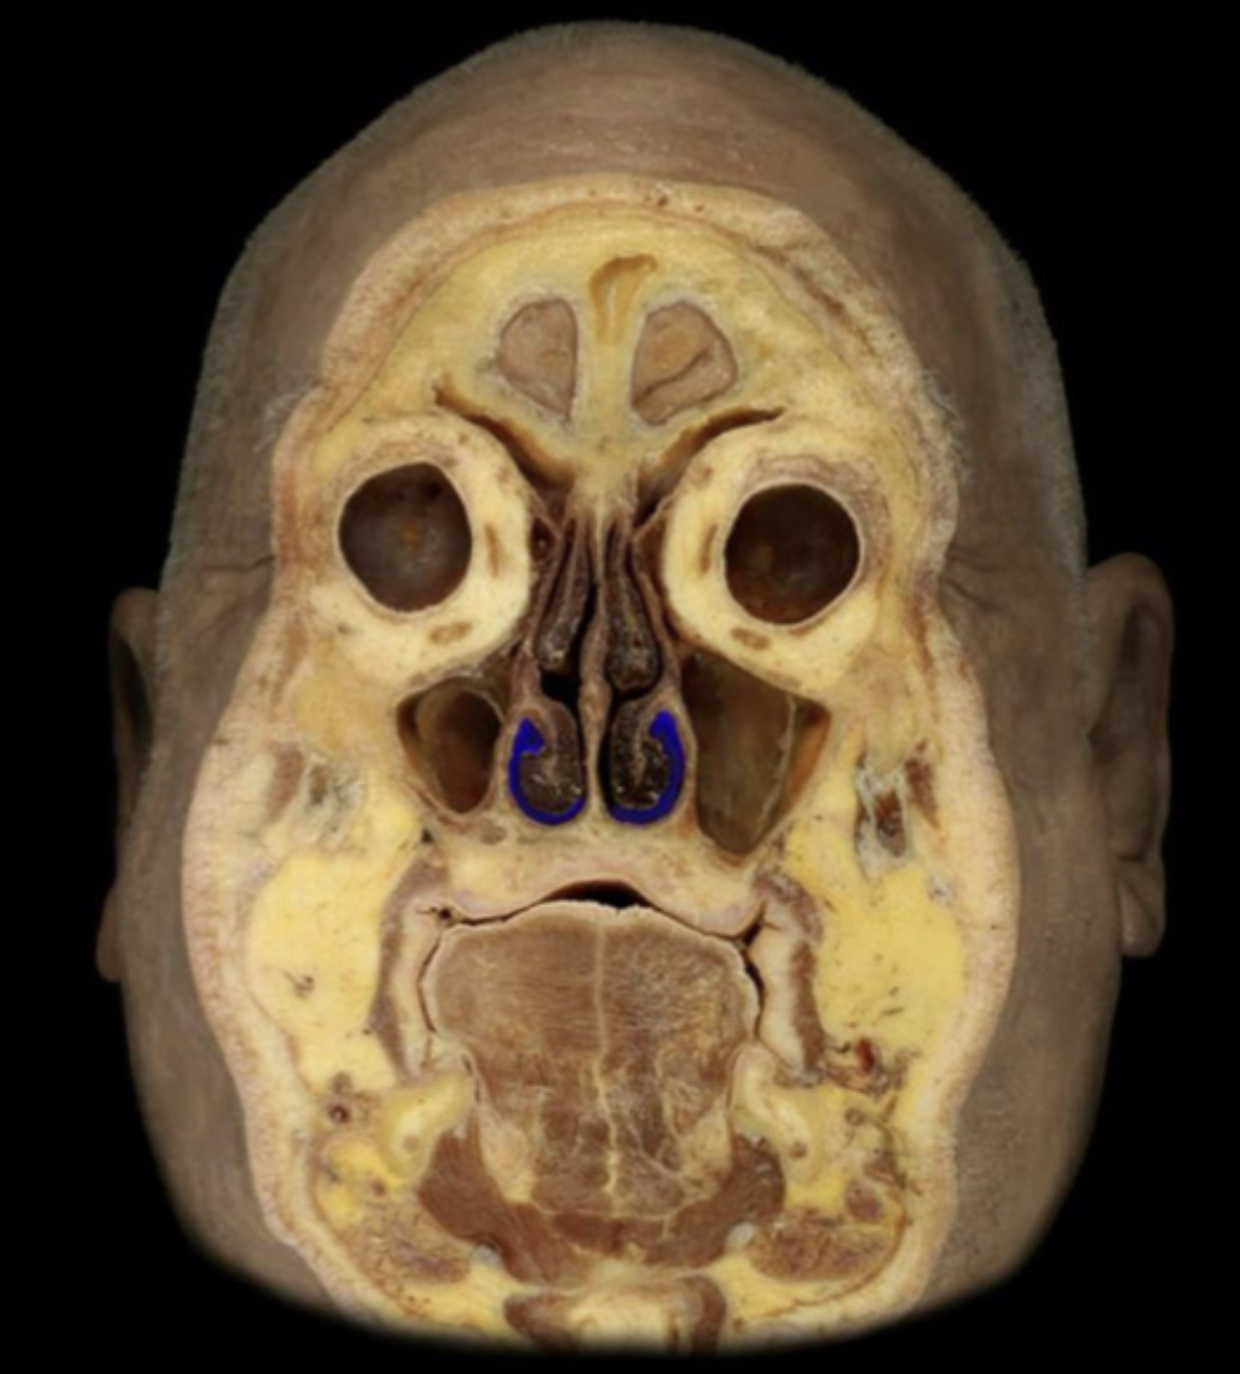

What structure is highlighted in blue?

Inferior nasal concha